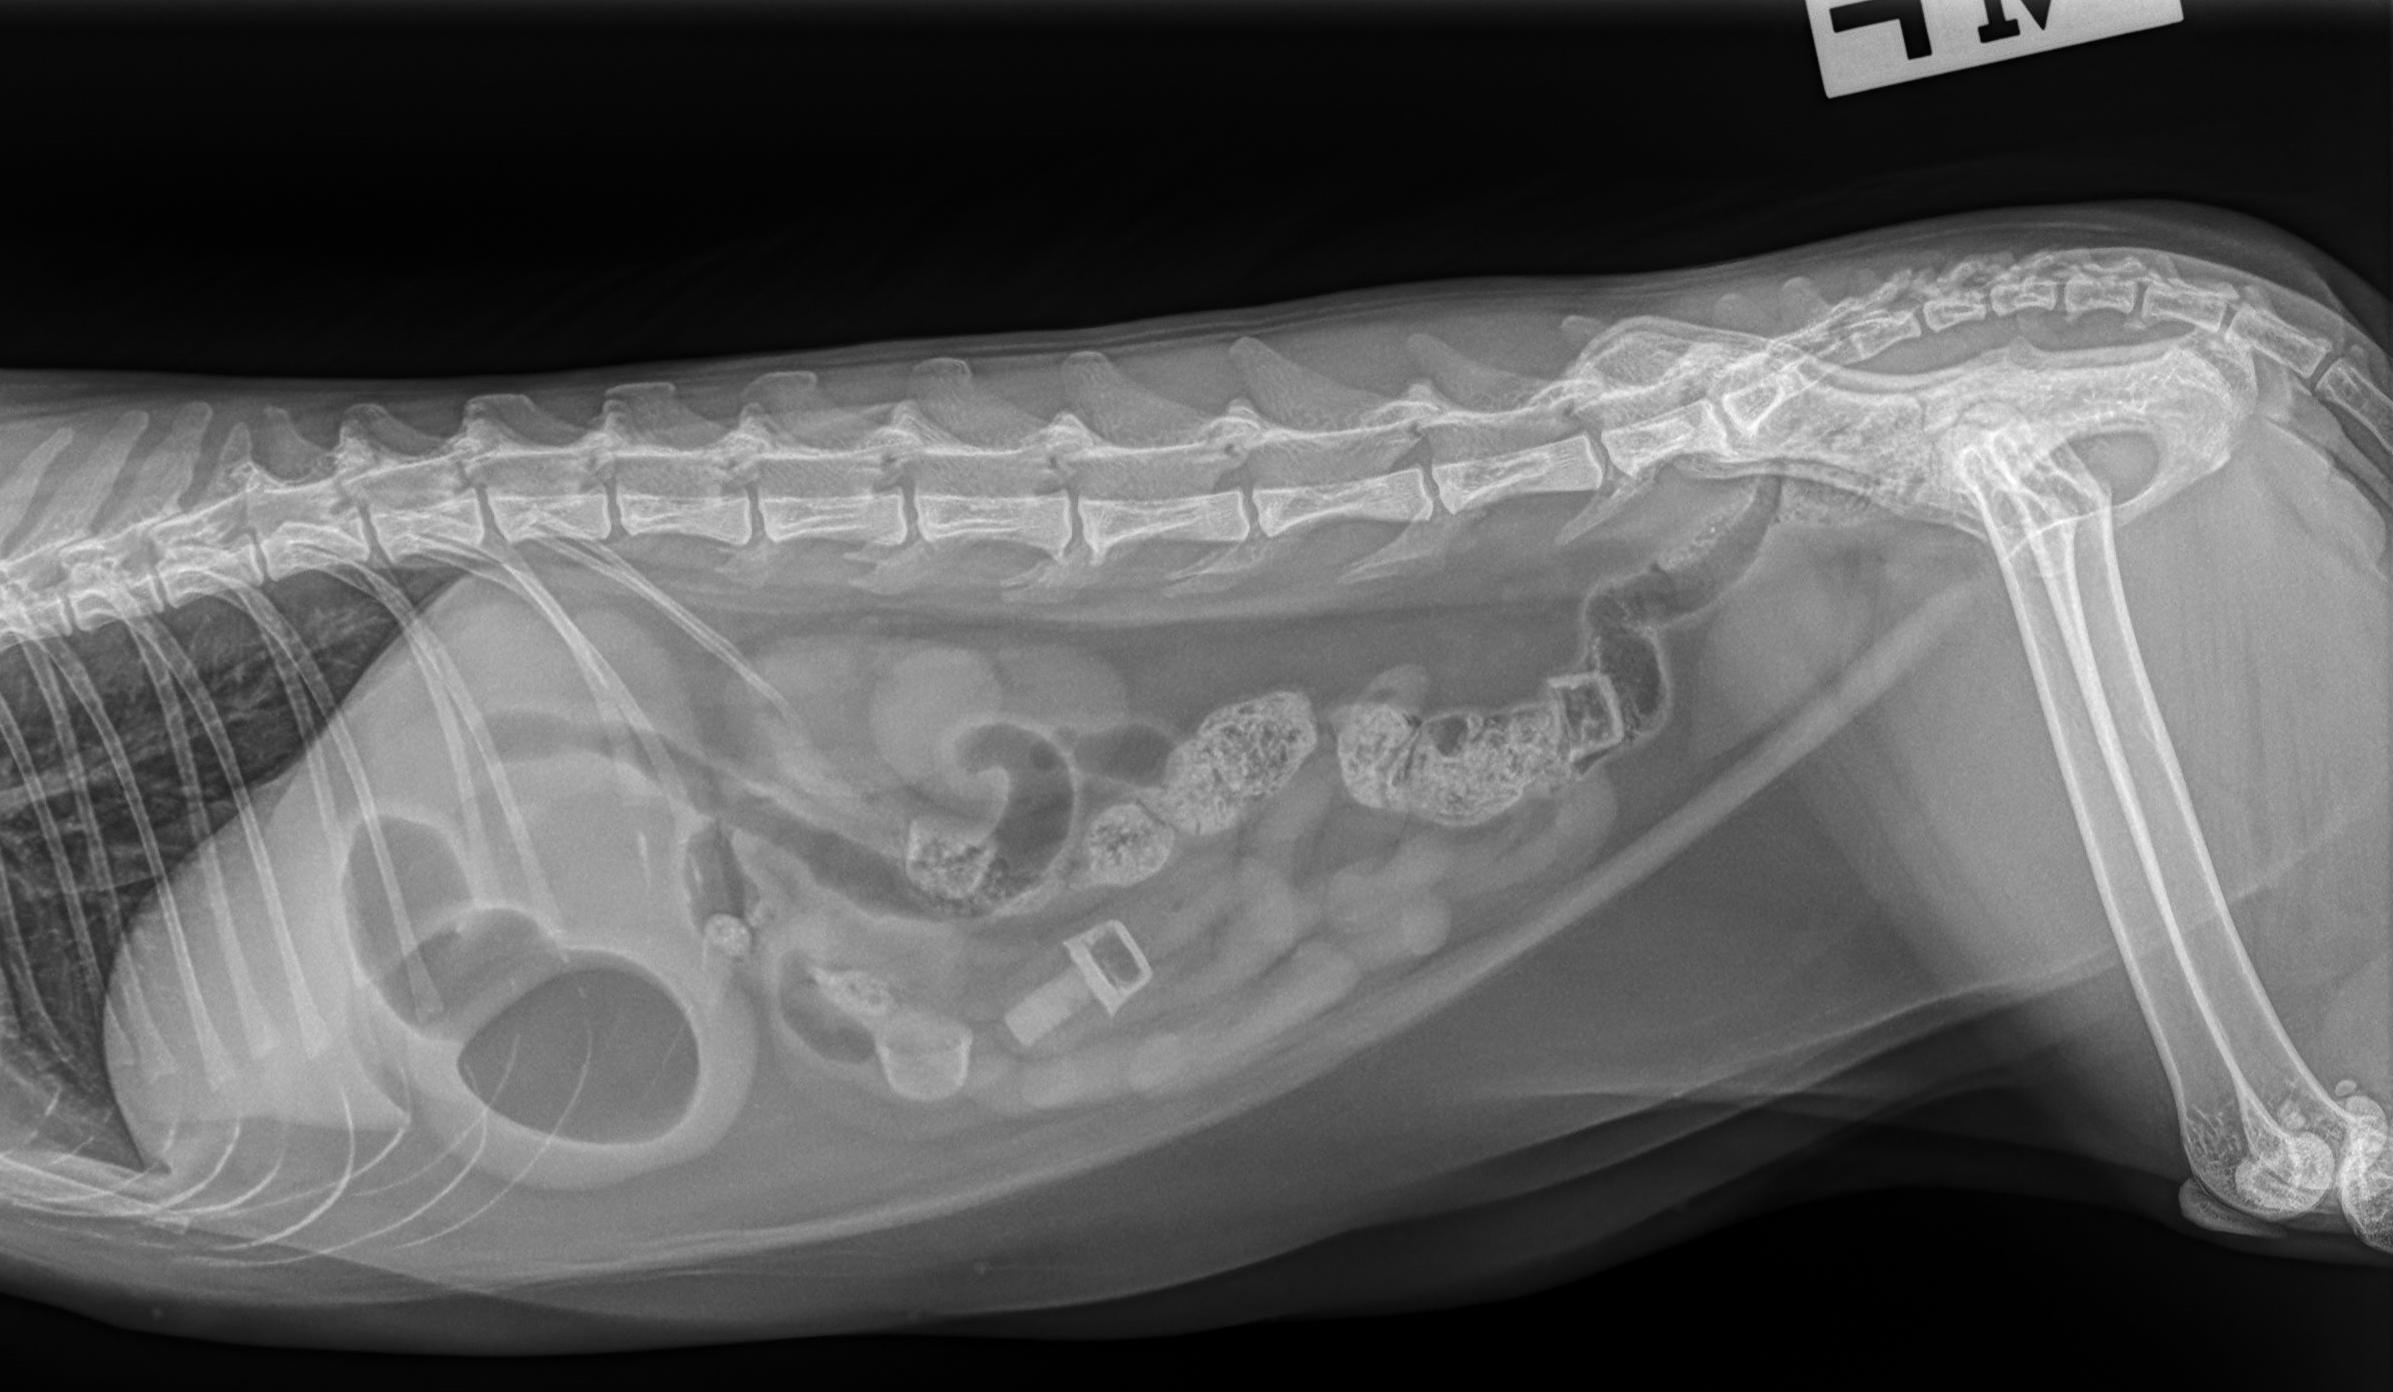

Beschrijving van de röntgenfoto's

Het serosale detail is binnen de normale grenzen. Er bevinden zich vier Nerf-kogels in het maagdarmkanaal: twee in het colon en twee in de dunne darm. Enkel het rubberachtige deel van de kogels is aanwezig en slechts één is volledig, van de overige is enkel het uiteinde zichtbaar. Er is een matige dilatatie van de maag met gas en vocht. De dunne darm is voornamelijk met vocht gevuld, met lichte gasdilatatie. De rest van het abdomen vertoont geen afwijkingen.

- Nerfgun-kogels in het maagdarmkanaal: Twee in de dikke darm, twee in de dunne darm.

- Opletten voor een mechanische obstructie, vanwege dilatatie van de maag en de dunne darm (minstens van partiële aard). De aanwezigheid van twee kogels in het colon kan echter wijzen op mogelijke spontane passage. Herhaalde abdominale radiografie en of abdominale echografie kan overwogen worden binnen 8 tot 12 uur, of eerder indien de patiënt klinisch verslechtert of niet verbetert, voor verdere evaluatie indien klinisch geïndiceerd. Als alternatief kan een chirurgische exploratie overwogen worden indien klinisch geïndiceerd.